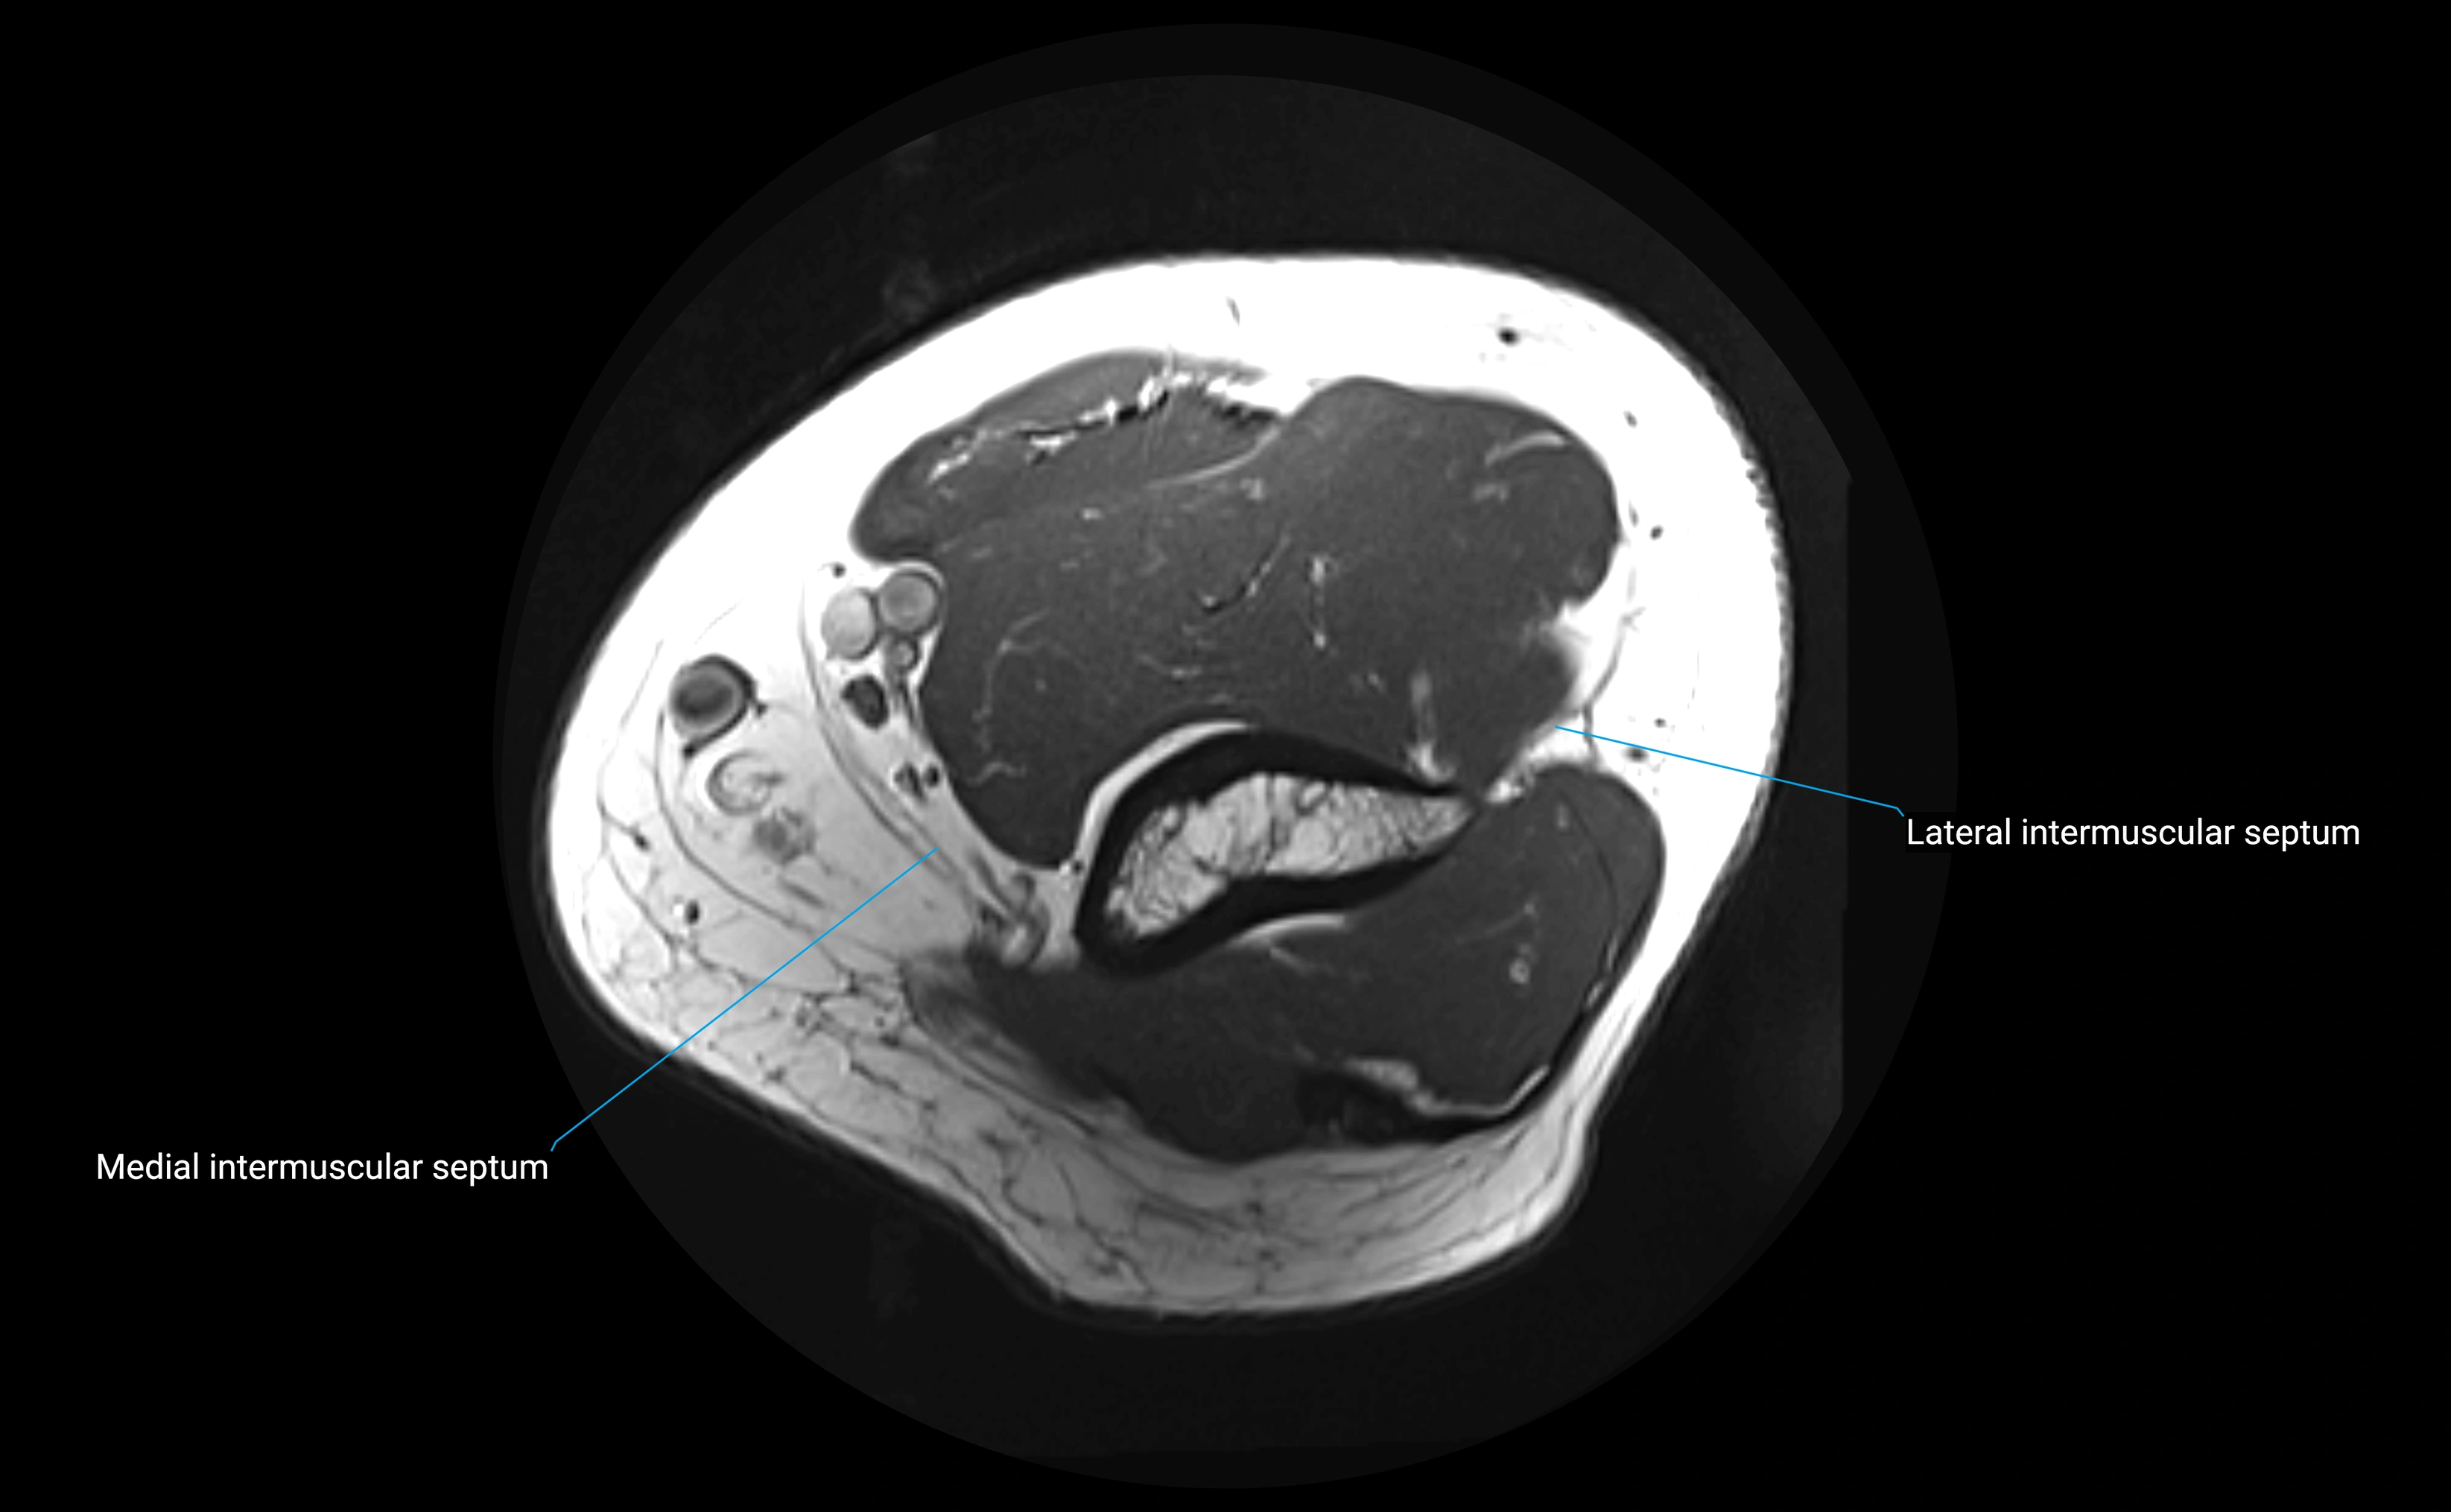

MRI Appearance

T1-weighted images:

• Ligament: low signal intensity (dark), appearing as a continuous band around the radial head.

• Adjacent fat and marrow: bright, creating contrast with the ligament.

• Thickening or disruption indicates injury or fibrosis.

• Joint capsule and synovium seen as thin low-signal lines contiguous with ligament margins.

T2-weighted images:

• Ligament: low signal (dark) with clear delineation from joint fluid.

• Fluid or edema: bright hyperintense, separating or surrounding the ligament in partial tears.

• Complete tear: discontinuity or non-visualization of ligament fibers, often with joint effusion.

STIR:

• Normal ligament: dark band encircling radial head.

• Pathology: bright hyperintense periligamentous signal suggesting edema, sprain, or partial tear.

Proton Density Fat-Saturated (PD FS):

• Normal: dark, well-defined band outlining the radial head.

• Partial tear: irregular or bright hyperintense signal within or adjacent to ligament fibers.

• Joint effusion and reactive synovitis appear bright and are well visualized.